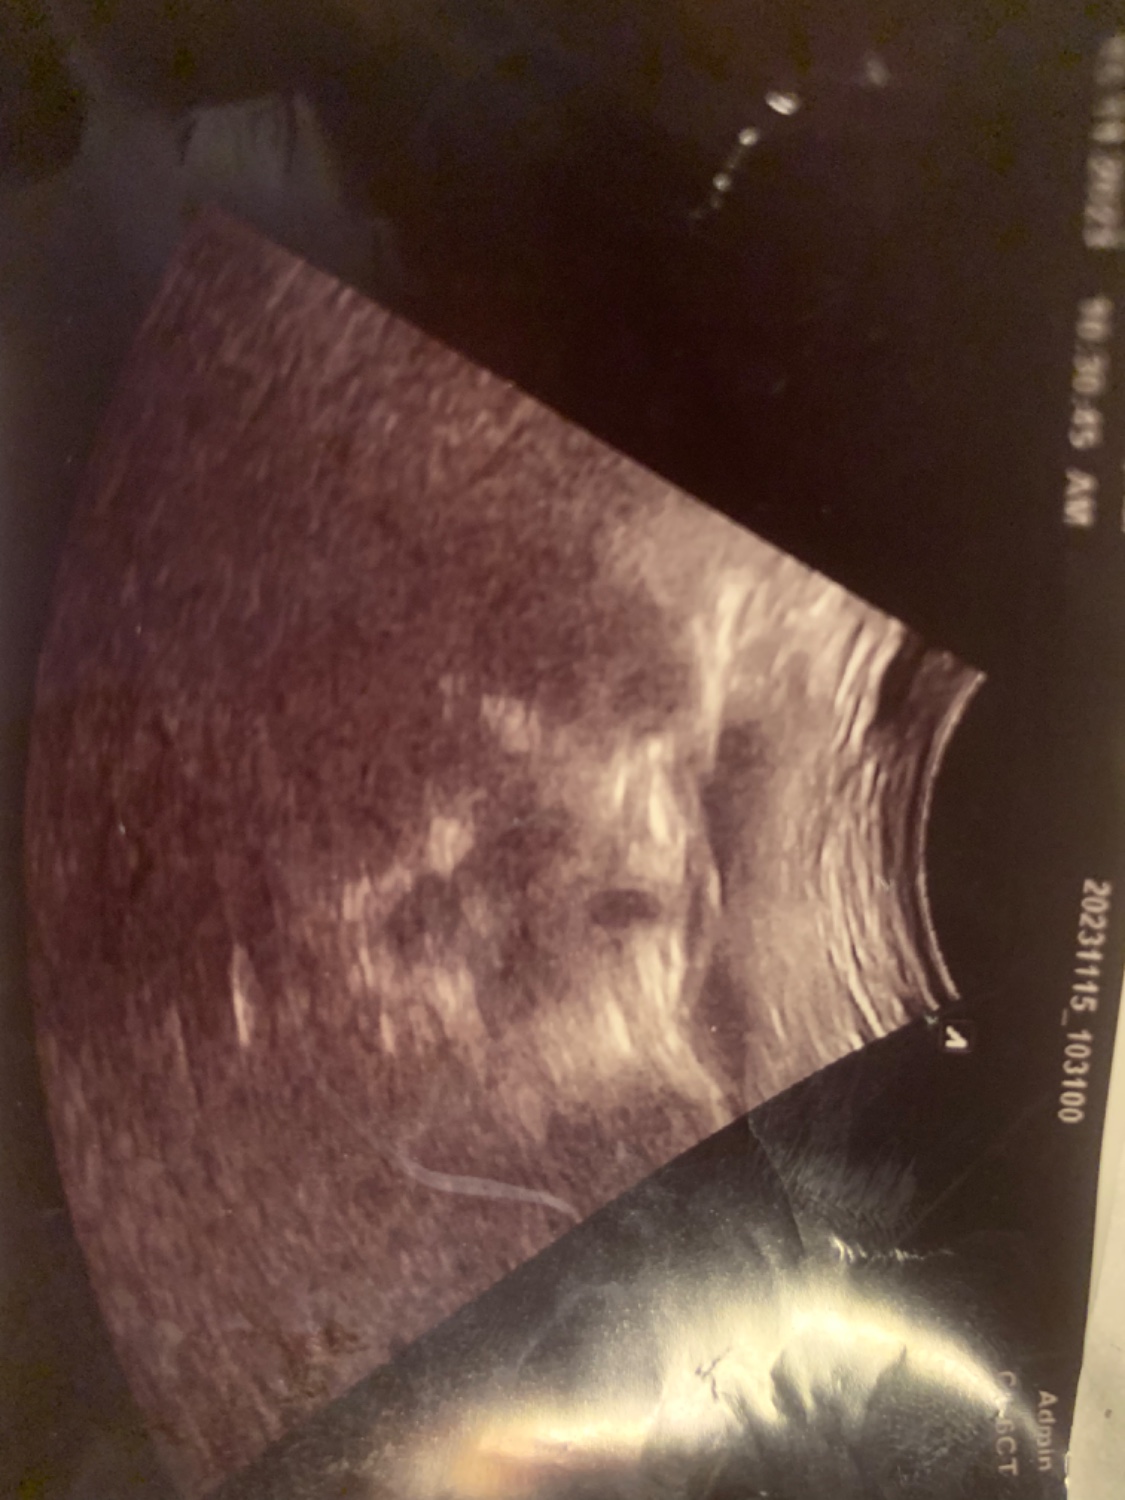

รบกวนช่วยดูผลตั้งครรภ์หน่อยค่ะ ซาวด์ผ่านททางช่องคลอด

เราไม่ทราบว่าตั้งครรภ์กี่สัปดาห์เพราะประจำเดือนไม่ค่อยมา หมอบอกไม่เห็นถุงตั้งครรภ์ แต่เห็นวงกลมๆที่ยังไม่แน่ใจว่าอะไร ตอนนี้รอฟังผลเลือดค่ะ